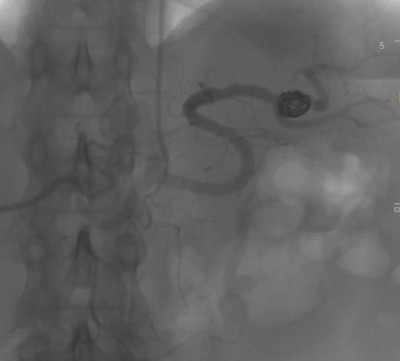

При большой или быстро растущей аневризме, при угрозе разрыва выбирается оперативное вмешательство. Предпочтение отдаётся малоинвазивным методам: эндоваскулярной (внутрисосудистой) хирургии: стентированию и эмболизации САС — закрытие полости выпячивания с помощью специальных материалов или препаратов. Вмешательства проводятся под рентген-контролем.